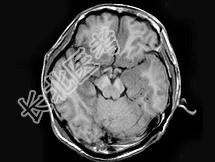

- 单项选择题男,46岁, 头痛、呕吐1周,MRI如图, 最可能的诊断是 ( )

A、脑梗死

B、病毒性脑炎

C、胶质瘤

D、化脓性脑炎

E、未见异常